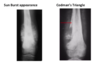

Most common malignant bone tumour. Usually **10-14** or **\>65** years in the **metaphysis of the distal femur or proximal tibia** **Localised constant pain** and tender soft tissue mass X-ray will show **medullary and cortical bone destruction with periosteal reactions** (Codman's triangle/Sunburst pattern) **Tissue biopsy** to diagnose then **aggressive surgical resection with systemic chemotherapy** as known to metastasise to lung